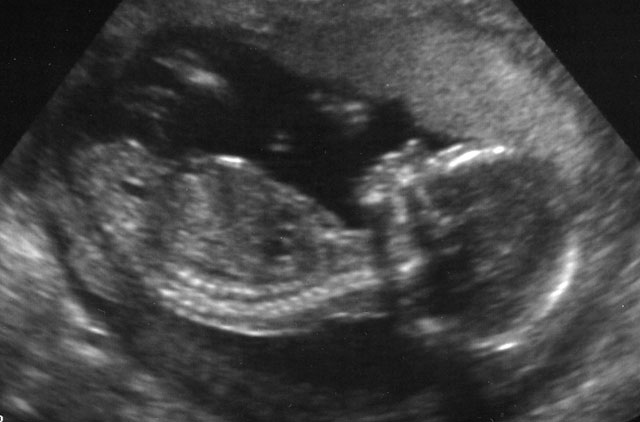

Surveillance photographs unable to find little willy, guess that means FunkyZorro will be painting the nursery in pink.

FunkyZorrette having a peaceful life inside, no cold winter with loads of snow and ice. Who doesn't want to live in an environment which is always 37C?